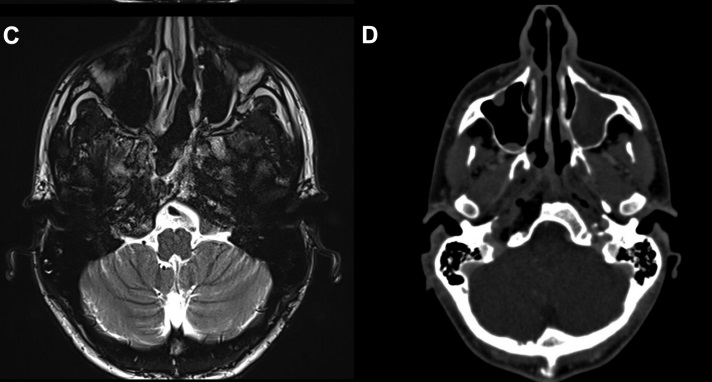

病情回顾:福教授一例复杂脊索瘤手术案例,这位病人的颅底脊索瘤较为复杂,长在了颅底斜坡、鞍旁、侵犯了海绵窦内的面部感觉及运动神经,并压迫脑干。位置及其复杂,手术风险较大,手术具挑战。患者情况危机急需手术,面对如此复杂棘手的脊索瘤,福教授会如何做手术决策?

在详细分析了肿瘤的位置及生长特性后,其主刀医生福教授为病人选择了神经内镜下经鼻手术入路可直接抵达肿瘤位置,风险较低。该病人海绵窦长在鼻腔之后距离约1cm,手术时福教授注意保护窦里的神经血管,用2小时得以暴露瘤体。颈内动脉就在这里附近,需要特别注意保护,破裂出血随时会有致命风险。

手术后较大部分的肿瘤被切除,很小部分瘤体和神经、血管、脑干等缠粘无法切除。术后病人将住院治疗8-10天。